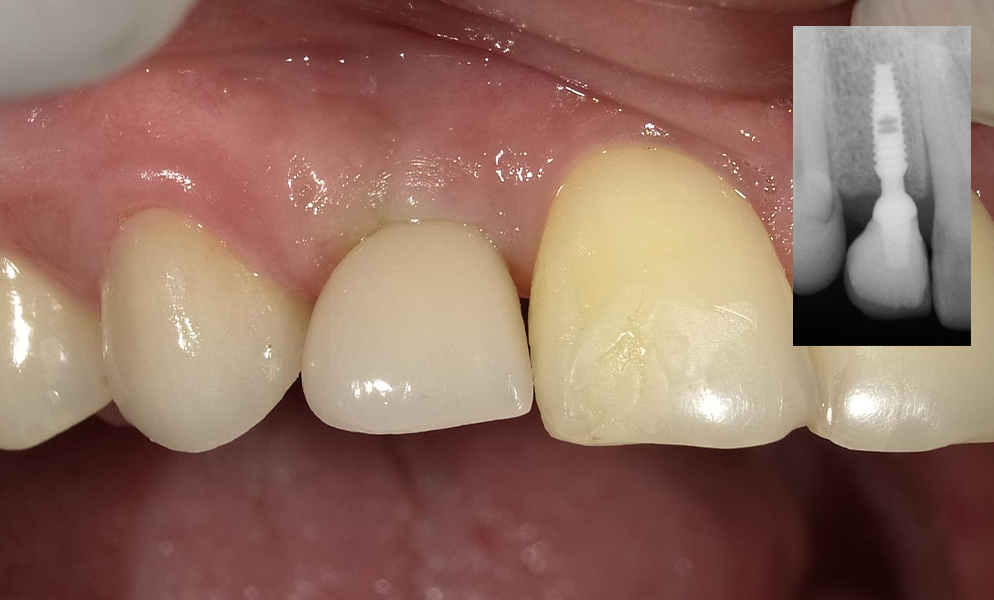

| Before | After |

![]() |

| Single anterior tooth missing space restored with a narrow dental implant (Bicon, USA) | |